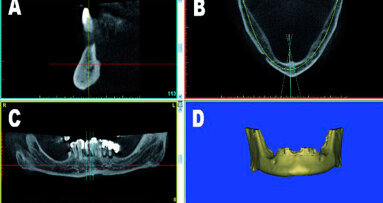

Mediante l’uso di modalità avanzate di imaging, si sono stabiliti nuovi paradigmi che, secondo l’opinione dell’autore, continueranno a ridefinire il processo di diagnosi e di pianificazione del trattamento circa le procedure implantari per gli anni a venire. Senza l’applicazione della tomografia computerizzata (CT) o della tomografia computerizzata cone beam a minor dosaggio (CBCT), non si può ottenere un’esatta comprensione della realtà anatomica tridimensionale, con aumento potenziale delle complicanze chirurgiche e restaurative. L’utilizzo di modalità di imaging in 3D come parte della pianificazione protesica pre-chirurgica può seguire diverse strade, come dimostrato nel diagramma di flusso. La prima prevede l’acquisizione di una scansione direttamente in 3D, senza alcuna pianificazione preventiva o apparecchiature accessorie. Il processo di scansione può essere realizzato in un centro di radiologia locale o tramite una macchina CBCT in studio, ora ampiamente disponibile. La scansione in sé può essere completata in pochi minuti. Una volta che i dati sono stati elaborati, possono essere visualizzati mediante il software della macchina CBCTutilizzata e valutati per potenziali siti riceventi implantari, seguìti dall’intervento chirurgico. Un secondo percorso richiede la realizzazione di un dispositivo scanner radiopaco che incorpora informazioni restaurative vitali e che sarà indossato dal paziente durante l’acquisizione della scansione. In questo modo si può valutare la posizione dei denti rispetto all’osso sottostante e ad altre importanti strutture anatomiche, come il seno mascellare o il nervo alveolare inferiore. Si possono visualizzare di nuovo i dati di scansione tramite il software originale della macchina CBCT e si può decidere un piano basato direttamente sulle esigenze restaurative del paziente.